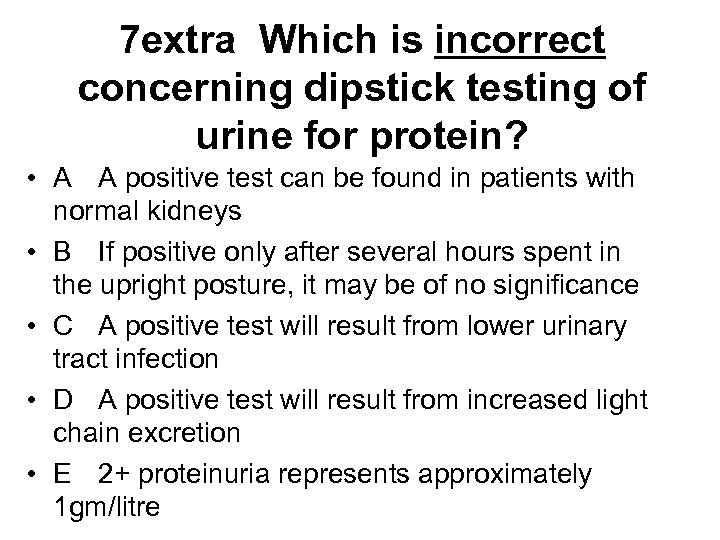

7 extra Which is incorrect concerning dipstick testing of urine for protein? • A A positive test can be found in patients with normal kidneys • B If positive only after several hours spent in the upright posture, it may be of no significance • C A positive test will result from lower urinary tract infection • D A positive test will result from increased light chain excretion • E 2+ proteinuria represents approximately 1 gm/litre

7 extra Which is incorrect concerning dipstick testing of urine for protein? • A A positive test can be found in patients with normal kidneys • B If positive only after several hours spent in the upright posture, it may be of no significance • C A positive test will result from lower urinary tract infection • D A positive test will result from increased light chain excretion • E 2+ proteinuria represents approximately 1 gm/litre

7 extra Which is incorrect concerning dipstick testing of urine for protein? • A A positive test can be found in patients with normal kidneys • B If positive only after several hours spent in the upright posture, it may be of no significance • C A positive test will result from lower urinary tract infection • D A positive test will result from increased light chain excretion • E 2+ proteinuria represents approximately 1 gm/litre

7 extra Which is incorrect concerning dipstick testing of urine for protein? • A A positive test can be found in patients with normal kidneys • B If positive only after several hours spent in the upright posture, it may be of no significance • C A positive test will result from lower urinary tract infection • D A positive test will result from increased light chain excretion • E 2+ proteinuria represents approximately 1 gm/litre